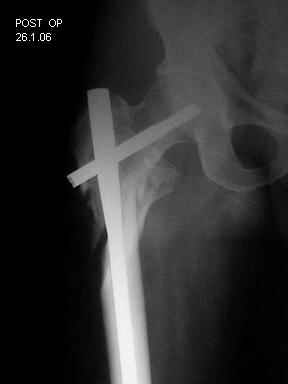

I choose Long Gamma Nailing and did it on 24.1.2006.

Now posting the post op x-rays for all of yours comments please. Don't hesitate to criticize me.

Congratulations. Virtually perfect. What reduction technique did you use? Looks like still traction table? To cavil to at least something looks like reduction is in microscopic varus - comparative x-rays can clear this - though only for academic interest with no clinical significance. Did you insert distal screws?